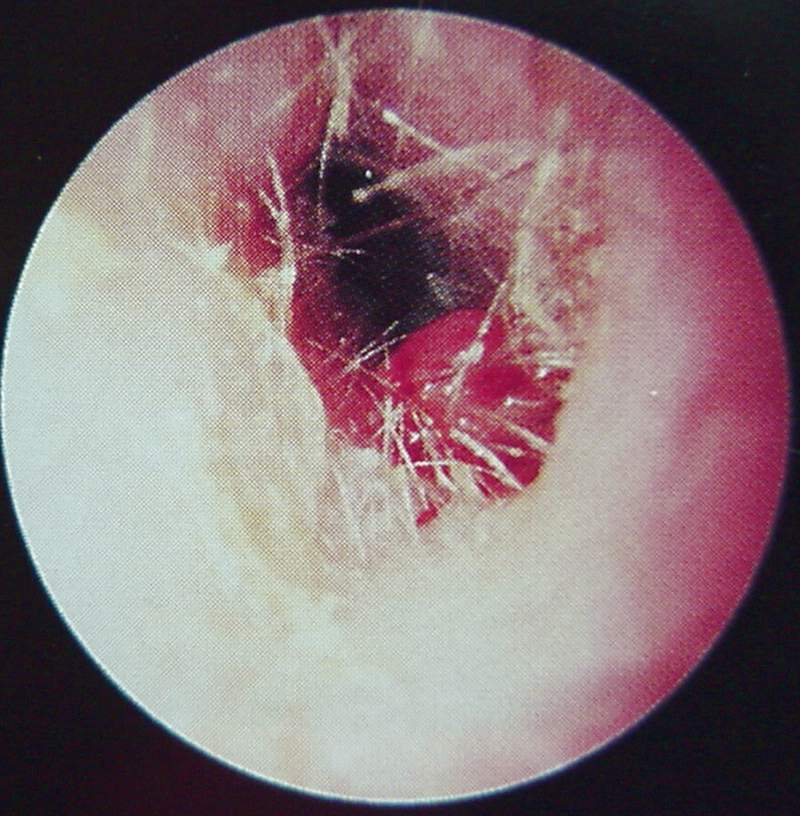

Ear Clinical Photos for Static Stations